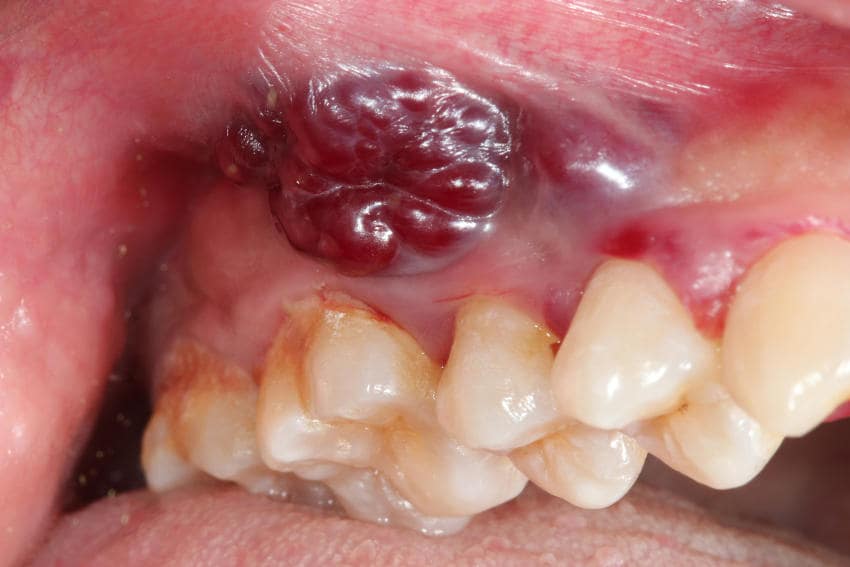

Le manifestazioni sulla cute consistono in lesioni di color rosso-violaceo sotto forma di

- macule (lesioni piane),

- papule (lesioni rilevate),

- placche e noduli (derivanti dalla confluenza delle papule);

le lesioni solo raramente sono associate ad altri sintomi (come dolore o prurito).

Questa forma del sarcoma di Kaposi si manifesta con lesioni cutanee piane (macule) tondeggianti o ovalari, rosso-violacee, asintomatiche, localizzate alle estremità degli arti inferiori (caviglie, piedi) e/o superiori (mani, polsi).

La comparsa avviene prima su unico lato del corpo, per poi svilupparsi simmetricamente anche all’altro lato; le macule possono evolvere ispessendosi e diventando papule (singole lesioni cutanee rilevate), noduli o placche (derivanti dalla confluenza delle papule).

Le placche hanno un tipico aspetto angiomatoso, ovvero un colore rosso-vino, contorni netti, forma irregolare e superficie liscia. Anche i noduli hanno queste caratteristiche e quando hanno dimensioni notevoli possono andare incontro ad ulcerazione.

- lesioni angiomatose (di colore rosso-vino) singole oppure multiple (forme floride) localizzate non solo agli arti superiori e inferiori (come nella forma mediterranea), ma diffusamente al tronco, volto, arti, mucosa orale, genitale e congiuntivale;

- la presenza di lesioni al palato puro e alla punta del naso è caratteristica del morbo di Kaposi epidemico (la presenza di lesioni nodulari alla mucosa orale e congiuntivale è indicativa di infezione da HIV avanzata).